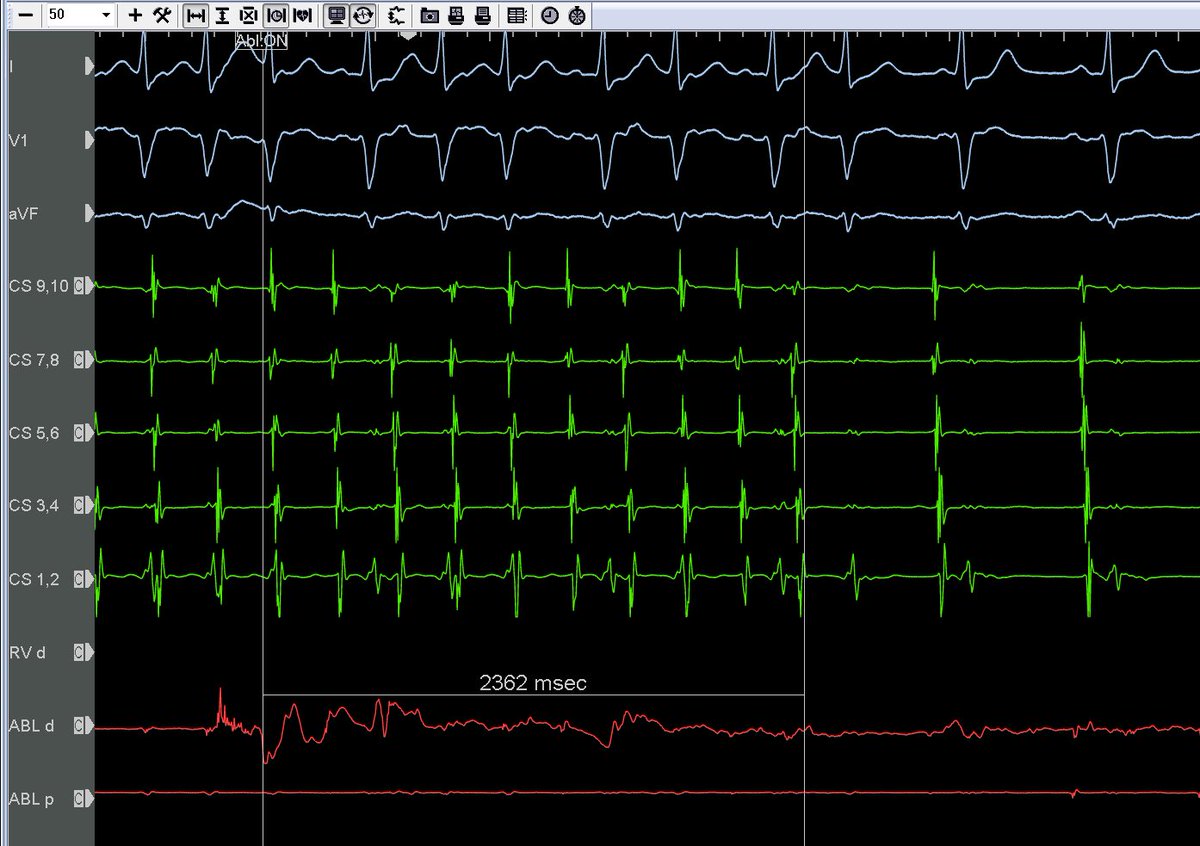

#EPeeps If you’re hungry for another #oneburnterm flex, keep scrolling, cause this ain’t one. ILR tracing causing abrupt syncope in 45ish yo man otherwise healthy